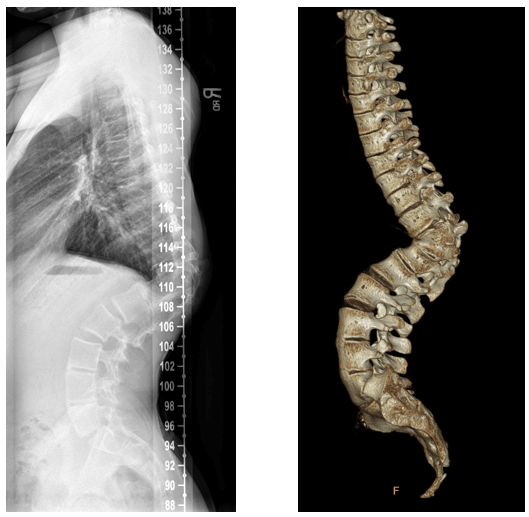

A 15-year-old boy diagnosed with congenital kyphosis and scoliosis as an infant was the first teenager to undergo a complex vertebral column resection surgery in Northeast Ohio. Over 12 hours, Michael Glotzbecker, MD, Division Chief of Pediatric Orthopaedic Surgery at UH Rainbow, partnering with Christopher Furey, MD, Chief of the Spine Center at UH Cleveland Medical Center, rebuilt the teen’s spine. The surgery involved two foot-long titanium rods, 16 screws, removing all of the bone 360 degrees around the spinal cord and an expandable cage to remove the curvature from the patient’s spine and the hump from his upper back. Dr. Glotzbecker is also Associate Professor of Orthopaedics at Case Western Reserve University School of Medicine.

“The goal of the VCR procedure is to remove all of the bone completely from around the spine (in front and behind the spinal cord),” Dr. Glotzbecker says. “This disconnects the spine above and below the curvature and allows us to correct severe, complex deformities. We then need the bone to grow within and around the cage, eventually encasing it in new bone and bridging the gap in the spine where it once curved. Clearly, this was unique and the first pediatric VCR at UH Rainbow and likely the most complex pediatric VCR done in Northeast Ohio.”

“EOSedge has several advantages,” adds Dr. Glotzbecker. “We get better information at a lower radiation dose. It allows you to get X-rays from the front and the side at the same time at a lower radiation exposure, and those images can be used to reconstruct images in three dimensions so you can actually get 3D modeling of the spine. For scoliosis and other spine conditions, this helps us in pre-surgical planning and ultimately, providing the best treatment. The only way to get 3D images without this technology would be a CT scan, which has significantly more radiation than a typical X-ray.”